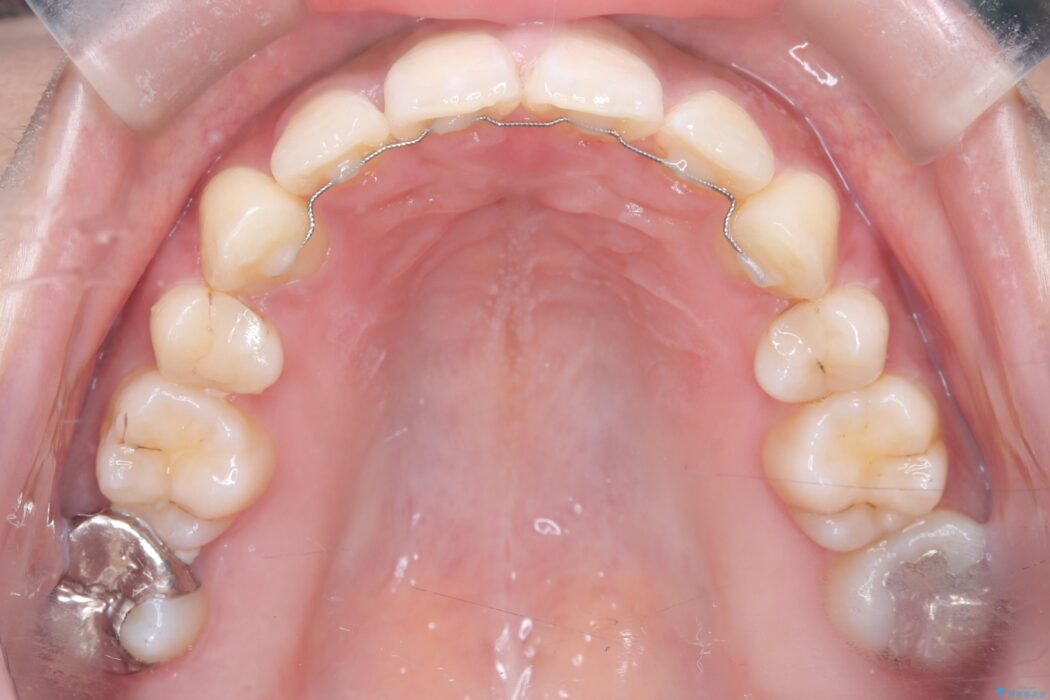

精密検査の結果、前歯を大きく後退させ、口元の突出感を改善するためには、スペースの確保が必要と診断しました。

そこで、上下左右の第一小臼歯(4番目の歯)を計4本抜歯し、そのスペースを利用して前歯全体を奥へ移動させる抜歯矯正の治療計画を立案。

確実な歯の移動を実現するため、ワイヤー矯正装置を使用しました。